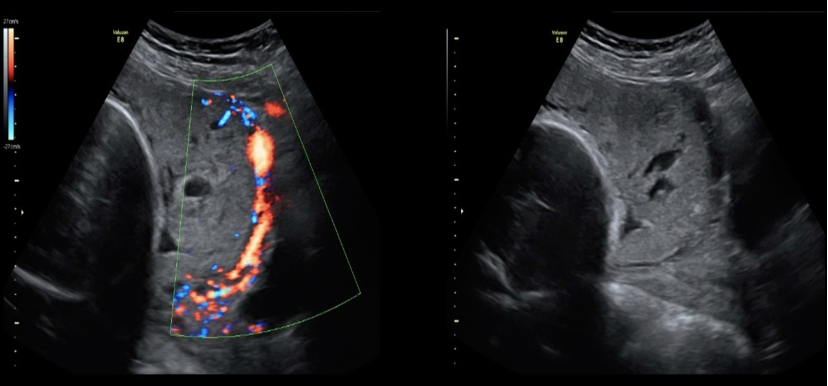

![<p>a) twin reversed arterial perfusion sequence [<strong>TRAP</strong>]</p><p>b) twin anemia polycythemia sequence (<strong>TAP</strong>)</p><p>c) a triploidy fetus + normal fetus</p><p>d) vanishing twin syndrome</p>](https://knowt-user-attachments.s3.amazonaws.com/93193faf-e189-4587-9739-07cd68e6222a.png)

a) twin reversed arterial perfusion sequence [TRAP]

b) twin anemia polycythemia sequence (TAP)

c) a triploidy fetus + normal fetus

d) vanishing twin syndrome

a) twin reversed arterial perfusion sequence